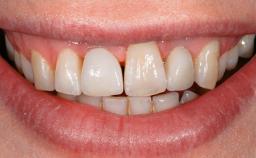

Oral Lichen Planus Associated with the Peri-implant Mucosa

This case describes the ongoing management of a 64-year-old healthy, non-smoking female patient with erosive oral lichen planus (OLP) affecting the gingivae and the buccal and lingual mucosa. The peri-implant mucosa was also affected subsequent to implant placement. The patient had osseointegrated implants (four in the maxilla, four in the mandible) placed following extraction of hopeless teeth and a healing period. The patient had a history of OLP prior to implant placement and had been referred to an oral-medicine specialist for definitive diagnosis and treatment. She exhibited generalized oral mucosal involvement. Following a clinical assessment, biopsy, and blood tests, she was treated with topical corticosteroids. Systemic prednisolone was reserved for severe flare-ups. Amphotericin lozenges were used in combination with corticosteroid treatment to prevent the development of oral candidiasis.